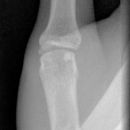

Grundgliedköpfchenfraktur